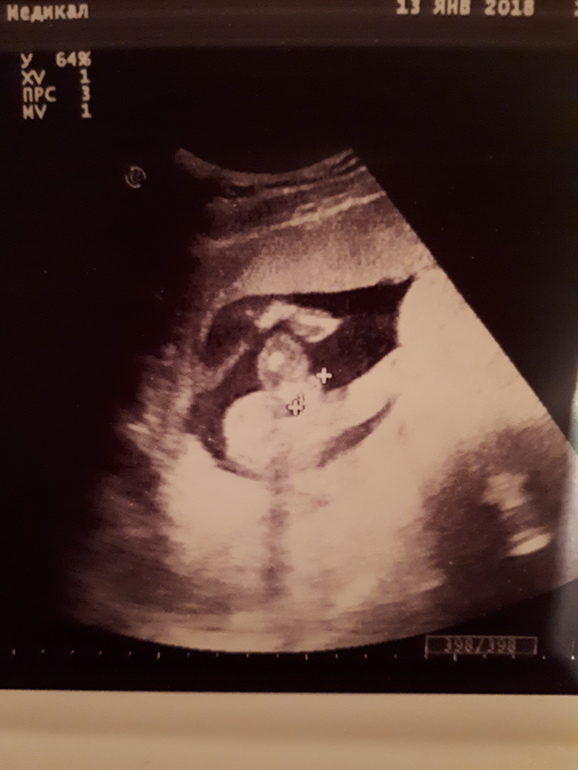

УЗИ, КТГ, доплерДевочки,привет!Возникло несколько вопросов,1.5 недели назад,узист на 95% сказала девочка,сегодня (17 полных недель) другой узист мальчик,как думаете?Ниже фото сегодняшнего узи.

И также сегодня сказали,что плацента на 43мм перекрывает внутренний зев,т.е.полное предлежание.Как так?1.5 назад ничего такого не было,ситуация так поменялась быстро?И сказала только половой покой и отдыхать побольше.У кого так было,поднялась?

На этом сроке надо уже фото снизу просить, чтобы именно две ноги и пися между ними, а на вашем фото не пойми что)))